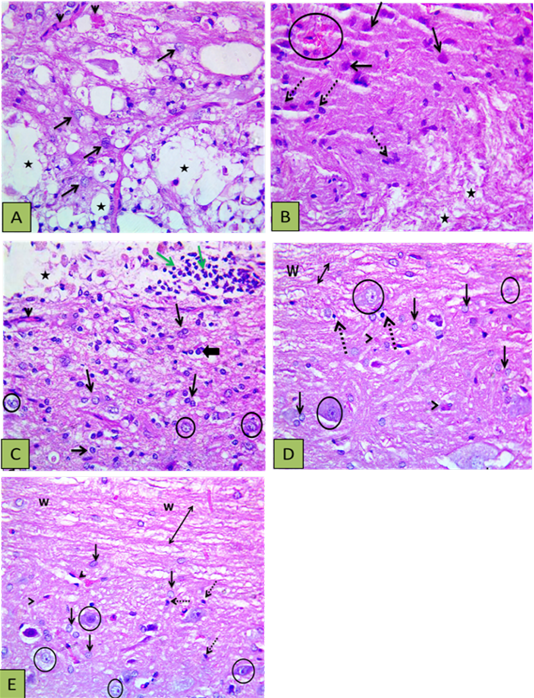

Showing histopathological findings. (A) Control group showing defective myelination (numerous areas of cavitation) (stars), reactive and increased size astocytes (arrows), and congested blood vessels (arrowheads); (B) Other section of control group showed the white matter with disrupted myelination (stars), the gray matter with numerous gemistocytic cells (reactive astrocytes shown by intact arrows), microglial cells proliferation (dashed arrows), and localized hemorrhage (circle); (C) PRP group showed astrocytic proliferation with increased size (reactive astrocytes) (thin arrows) oligodenrocytes (thick arrow), mild vascularity (arrowheads), with light stained intact neurons (circle) and white matter disruption (vacuoles shown by star) with inflammatory cells infiltration (green arrows); (D) BM-MSCs group showed intact axons (double heads arrow ) within white matter (w) and the grey matter showing astrocytic proliferation with increased size (blck arrows), oligodenrocytic proliferation (dashed arrow) minimal vascularity (arrowheads), with light stained intact neurons (circle); (E) PRP+BM-MSCs showing well myelinated nerve cells (upper side) (double heads arrow) within the white matter (w), astrocytic proliferation with increased size (intact arrows), microglia proliferation (dashed arrow) minimal vascularity (arrowheads), with light stained intact neurons (circle). H and E Photomicrograph with X400.